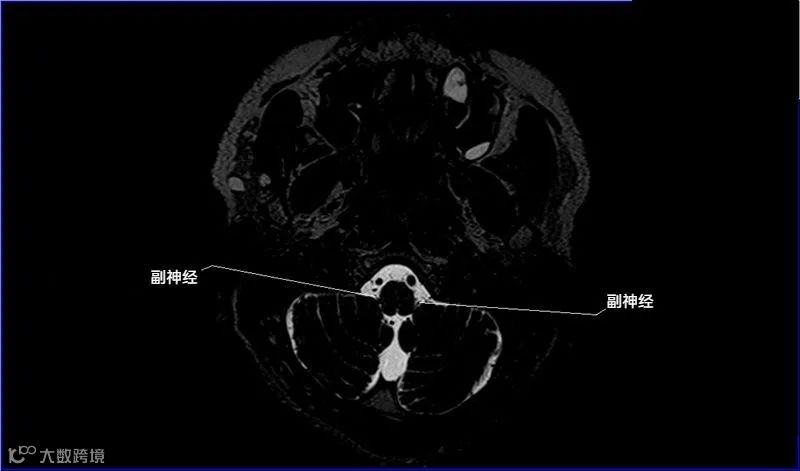

一嗅二视三动眼,四滑五叉六外展,

七面八听九舌咽,迷走及副舌下全。